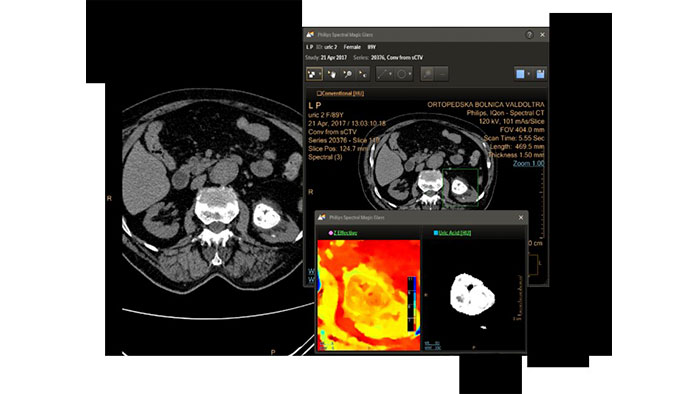

CT Spectral Light Magic Glass

Review spectral data in a range of not spectral-enhanced CT applications

Allows retrospective use of spectral data that was saved in a series of spectral base images (SBI).

The fast launch of LMG allows review and identification of the most relevant results to be launched into the application for further analysis.

Benefits

- The option is available from the following applications: Brain Perfusion, Functional CT, Liver Analysis, PAA, TAVI, Acute Multifunctional Review, Virtual Colonoscopy.

- Spectral Magic Glass can be launched only for CT images or images created on the Philips IQon Spectral CT.

CT Spectral Magic Glass on PACS*

IQon Spectral CT Functionality

IQon Spectral CT is the only scanner to offer CT Spectral Light Magic Glass and CT Spectral Magic Glass on PACS, helping radiologists review and analyze multiple layers of spectral data at once, including on their PACS.

Benefits

- On-demand simultaneous analysis of multiple spectral results for an Region Of Interest (ROI).

- Integrates into a health system’s current PACS setup for certain PACS vendors.

- Spectral results viewable, during a routine reading.

- Enterprise-wide spectral viewing and analysis allows access to capabilities virtually anywhere in the organization.

* Standard with the CT Spectral option on IntelliSpace Portal.